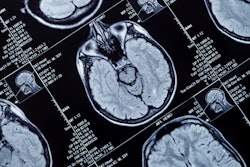

Researchers have found that MRI reveals functional brain alterations that are associated with major depression, according to a study published February 19 in JAMA Network Open.

Previous research using functional and structural MR imaging has explored the neurobiological mechanisms of depression and has noted depression-related alterations, such as hippocampal volume reductions and increased amygdala activity during emotional tasks. But it's still unclear "how far these alterations persist and whether prior exposure to depression affects brain function and structure later in life," the group wrote.

The investigators assessed the number of depression criteria study participants met, ranging from one to six. They calculated functional MRI measures using "voxel-wise fractional amplitude of low-frequency fluctuation (fALFF), global correlation (GCOR), and local correlation (LCOR)," and structural brain measures using gray matter volume (GMV).

The team found that, across all depression criteria, study participants with lifetime depression showed consistent decreases in fALFF, LCOR, and GCOR but not in gray matter volume. Those who had been identified with Hospital ICD-10 diagnosis codes F32 and F33 and antidepressant use had the most alterations in these measures.

"We found significant alterations in all functional and structural measures for most lifetime depression groups, except in patients who met all 6 criteria or met only 1 criterion when using GMV and GCOR," the group reported.

"Results of this cross-sectional study indicate that lifetime exposure to depression was associated with robust functional changes, with a more restrictive depression definition revealing more pronounced alterations," the authors concluded.